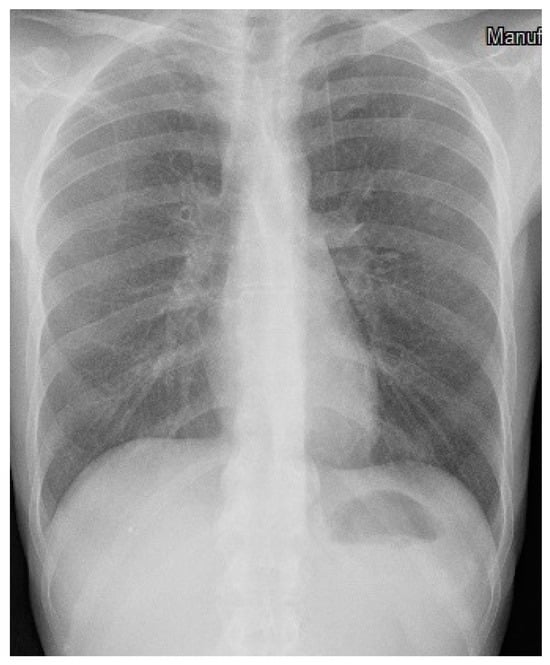

3. Case Description

4. Clinical Case Management